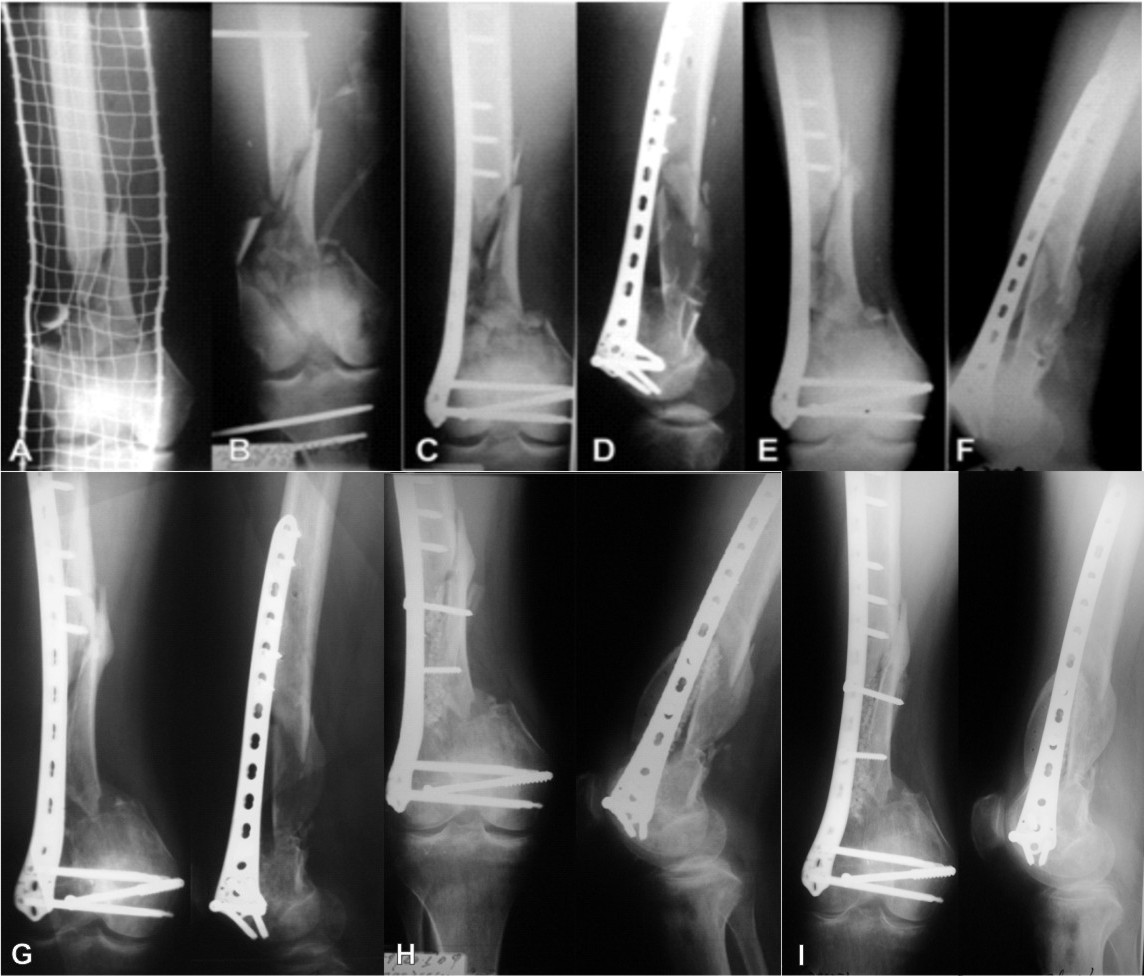

Case 1. A Primary reconstruction with plate and Kwire osteosynthesis Meaning Plate Osteosynthesis It is widely accepted to achieve bone healing with a dynamic and biological fixation where the. It is widely accepted to achieve bone healing with a dynamic. The advantages of minimally invasive plate osteosynthesis of the femoral shaft are lessening of the extent of muscle detachment and reduced compromise of bone vascularity. Plate osteosynthesis is one treatment option for the. Meaning Plate Osteosynthesis.

From www.semanticscholar.org